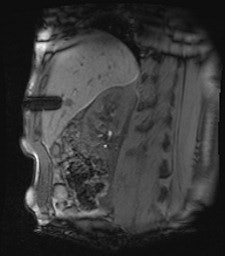

All procedures were performed using a wide-bore 1.5-tesla MR system (Magnetom Espree, Siemens Healthcare). A radiofrequency-shielded liquid-crystal display monitor was installed next to the magnet for real-time monitoring. During the procedures, imaging was performed with the use of a flexible four-channel body-array surface coil and a loop coil, and biopsies were performed with MR-compatible puncture needles. To obtain the specimen, an MR-compatible biopsy device (MRI Biopsy Handy, Somatex Medical Technologies) was used in 36 cases. After placing the MRI-compatible puncture needle in the magnet, two intramuscular biopsies were performed using a non-MR-compatible spring-loaded biopsy gun (ASAP, Boston Scientific) outside the magnet. During the biopsy, vital parameters were monitored using an MR-compatible patient monitor (Invivo 4500 MRI, Invivo Research).

In nine cases -- eight soft-tissue, one liver -- MR fluoroscopy was used to define the entry site, and the physician used a fingertip or water-filled syringe as a marker. In 29 cases -- 11 soft-tissue, 18 liver -- a marker capsule (Adalat, Bayer) was affixed to the supposed entry side with adhesive tape, and the position was corrected after application of conventional sequences. After sterile draping, administration of local anesthesia and skin incision, an MR-compatible puncture needle (14-18 G) was placed subcutaneously outside the magnet.